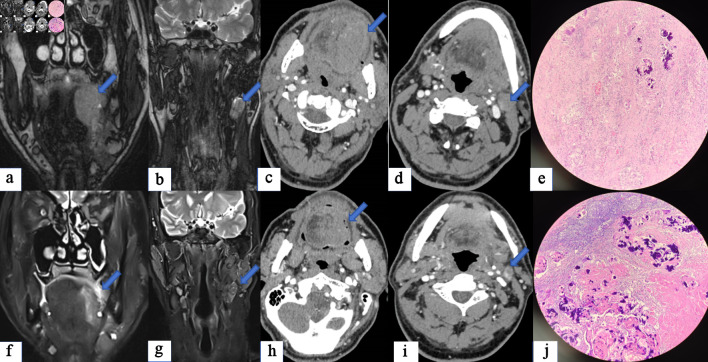

Background: We here investigated the value of imaging examination in evaluating tumor remission-based surgery in patients with head and neck squamous cell carcinoma (HNSCC), who had undergone neoadjuvant immunotherapy combined with chemotherapy (NICC).

Methods: HNSCC patients who underwent NICC and surgery from May 2021 to September 2023 were retrospectively analyzed. All patients had to undergo imaging examination evaluation, including enhanced computed tomography (CT) and enhanced magnetic resonance (MR) imaging before and after NICC. Data related to clinical parameters, complete response of the primary site (PrCR), complete response of the primary site and the lymph node (PLCR), complete response of the lymph node (LCR), and tumor response (TR), were gathered. The paired Chi-square test and t-test were conducted to analyze the differences in responses between imaging examination and pathology. Binary logistic regression was applied to analyze the relevant clinical factors of differences in responses.

Results: In total, data of 41 patients were included in this study. Significant discordant responses were observed between enhanced CT, magnetic resonance imaging (MRI), and pathology in PrCR (4.9%, 7.3% vs. 41.5%), LCR (12.2%, 7.3% vs. 53.7%), PLCR (0%, 0% vs. 31.7%), and TR (severe 29.3%,17.1% vs. 25.61%) (P < 0.05). Patients with hypopharyngeal cancer (odds ratio (OR): 7.04), oral cancer (OR: 3.64), higher neutrophil to lymphocyte ratio (NLR) (OR: 2.05), and earlier T stage (OR: 0.71) exhibited a larger response difference between enhanced CT and pathology. Patients with younger age (OR: 0.79) hypopharyngeal cancer (OR: 22.81), oral cancer (OR: 2.65), higher NLR (OR: 19.47), and earlier T stage (OR: 0.29) exhibited a larger response difference between enhanced MR and pathology.

Conclusions: Discordant responses were noted between the imaging examination and surgical pathology of HNSCC after NICC. Hypopharyngeal cancer, higher NLR, and earlier T stage may predict a higher response difference.